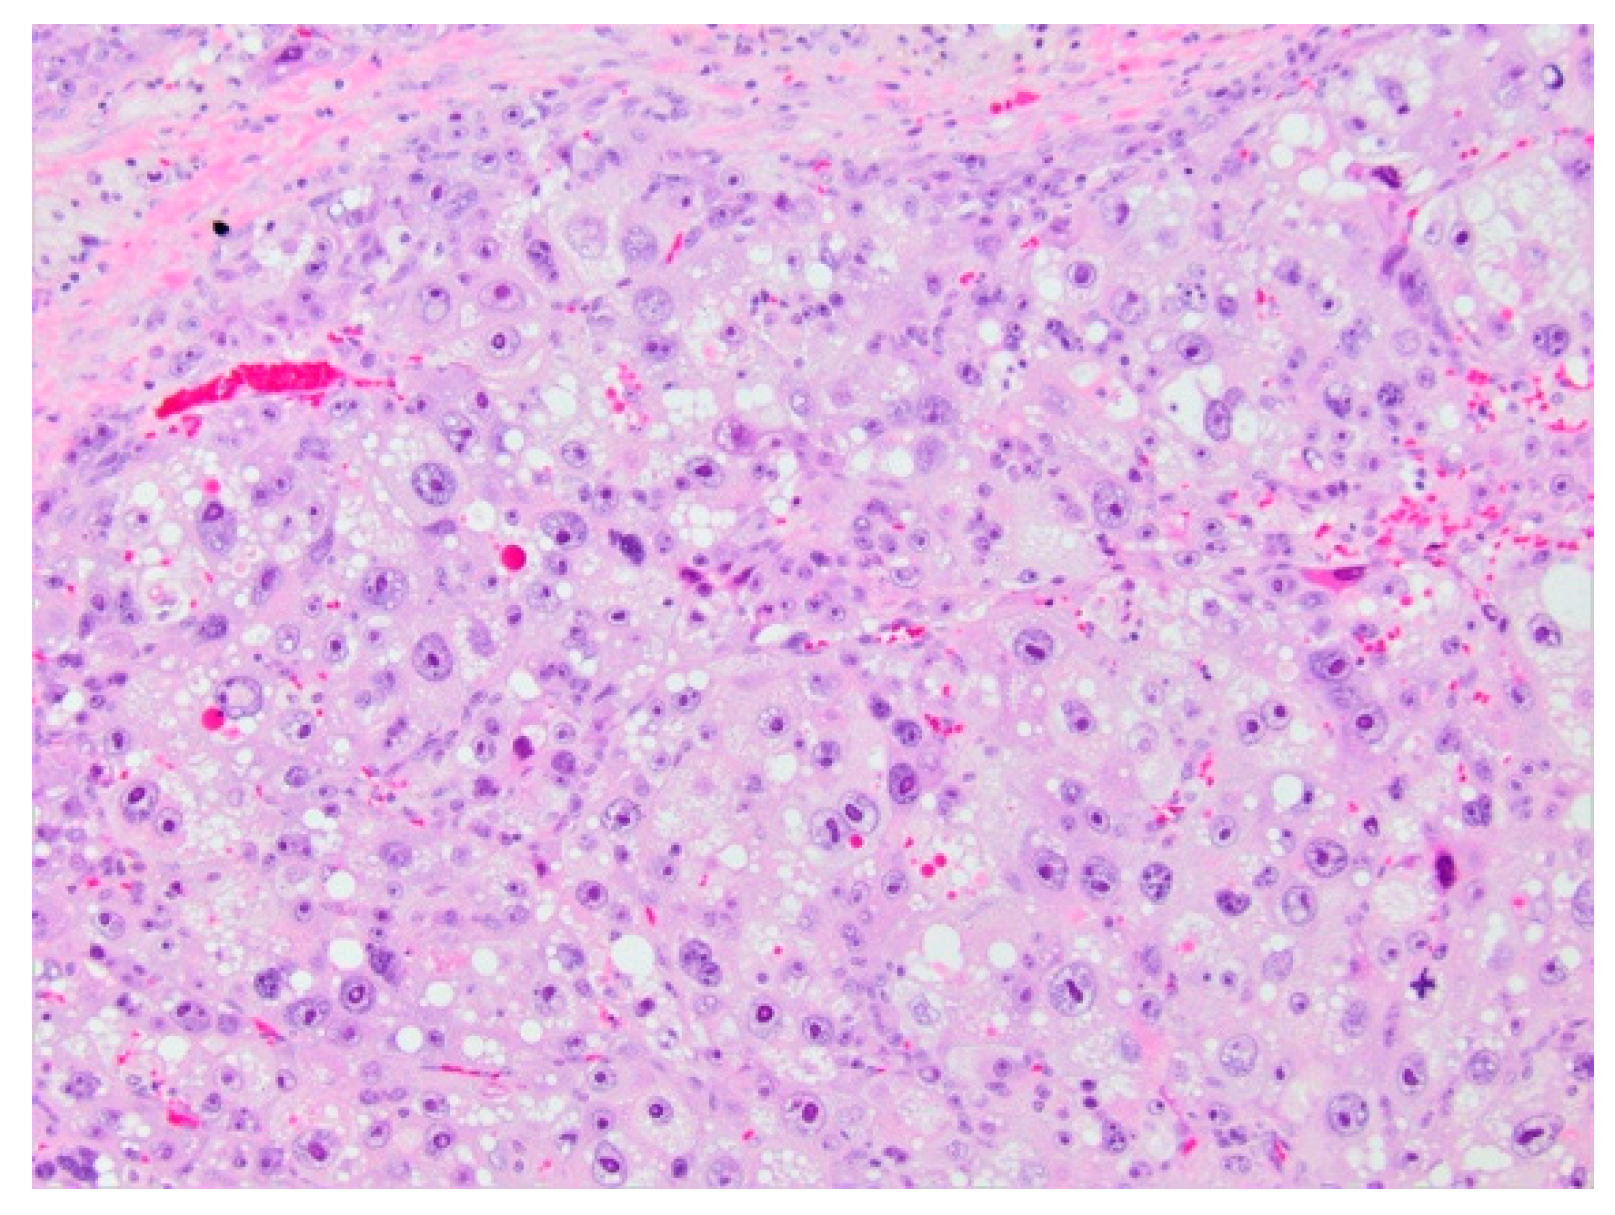

5.2.5. Histopathology and Immunohistochemistry